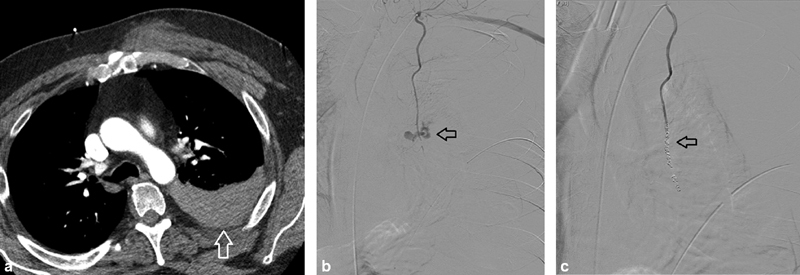

Fig. 1.

A 66-year-old man with intercostal hemorrhage following bedside chest tube placement by pulmonary medicine. Hemothorax developed requiring large bore (28 Fr) chest tube placement by cardiothoracic surgery. ( a ) Angiography demonstrates active extravasation of contrast from the right T intercostal artery (arrow). ( b ) Resolution of active extravasation of contrast following embolization with 700–900 micron Embosphere particles (Merit Medical Systems, South Jordan, UT). ( c ) Cessation of flow in the distal intercostal artery following coil embolization with Ruby micro coils (black arrow) (Penumbra Medical, Alameda, CA). A pigtail chest tube is also noted (white arrow).